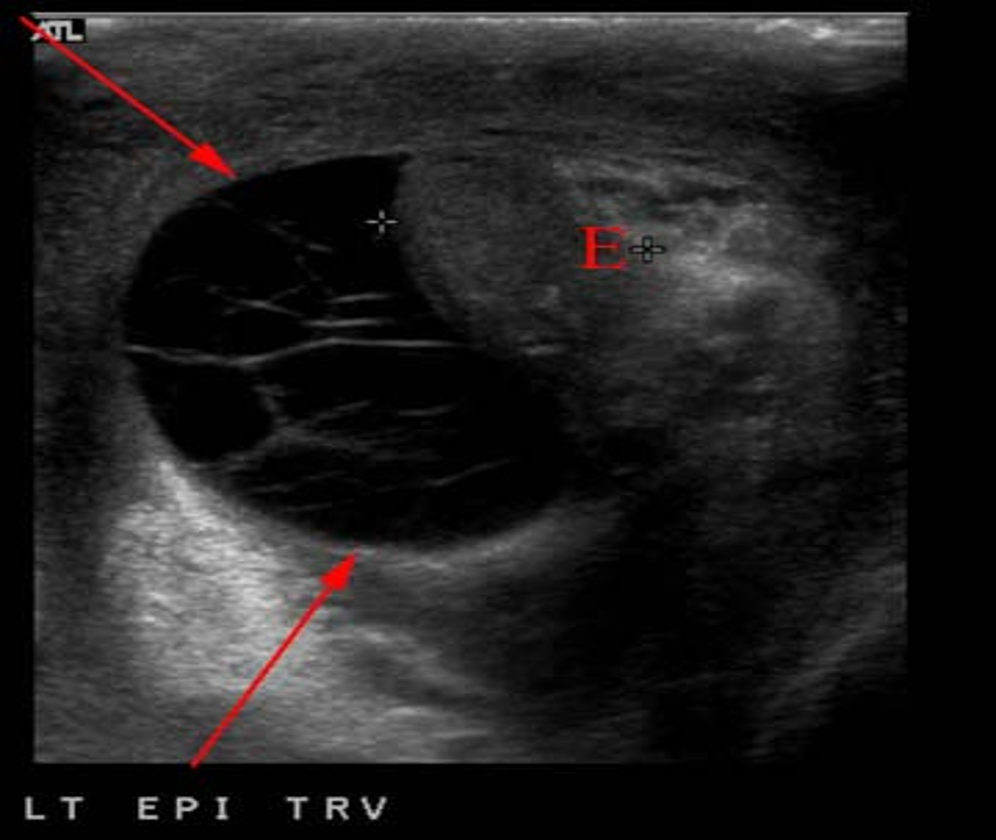

COMPLEX HYDROCELE